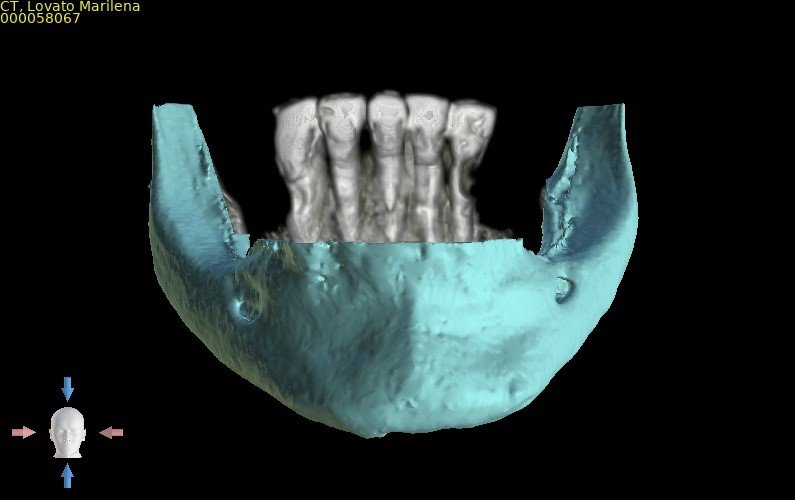

Paciente do sexo feminino, 82 anos, com a presença de dentes anteriores de mandíbula usando prótese móvel na região posterior por mais de 30 anos. Com isso, a reabsorção óssea posterior causou um desnível muito grande em relação à região anterior.

Através do programa Blue Sky (em parceria com a empresa Odontoplanning), foi feito planejamento guiado com 2 guias. O primeiro guia de recorte ósseo, tem como objetivo o recorte e aplainamento ósseo, deixando uma altura óssea mais uniforme entre a região posterior e anterior da mandíbula.

Através da imagem do osso recortado é planejada a guia de perfuração que vai se encaixar de uma maneira perfeita no osso recortado.